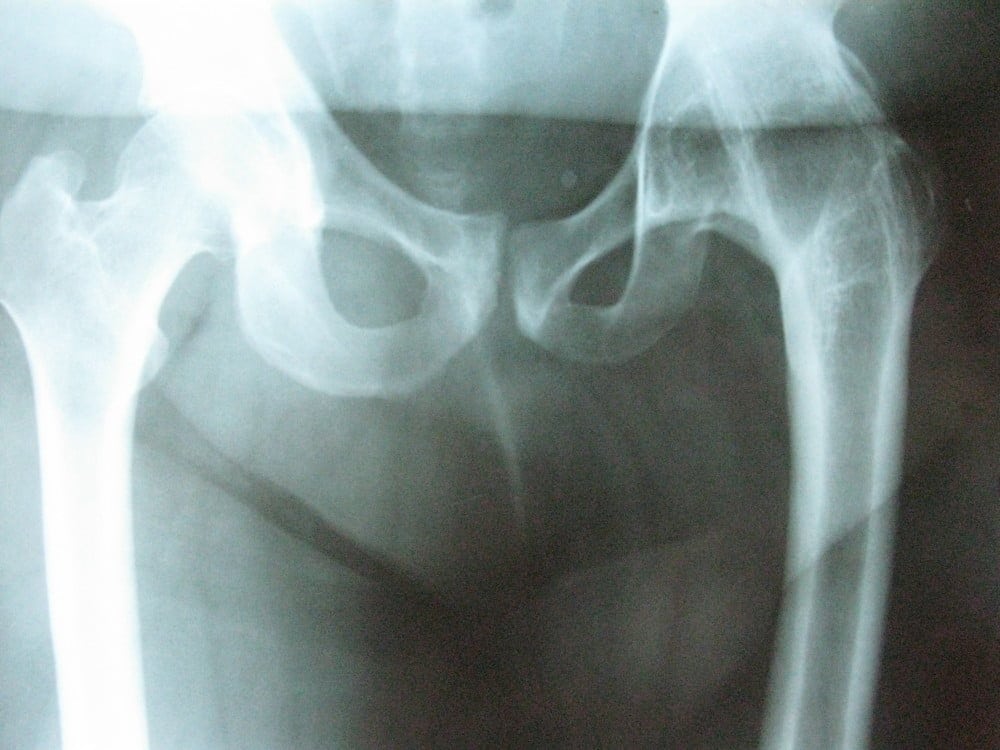

Коксартроз самой тяжелой степени устанавливается на основании ведущих симптомов, жалоб пациента. Косвенным подтверждением становятся заболевания тазобедренного сустава в анамнезе. Наиболее информативно рентгенологическое исследование. На снимках, полученных в двух проекциях, визуализируются практически все деструктивно-дегенеративные изменения:

- остеофиты — костные разрастания на краях хрящевой пластинки;

- полное или частичное сращивание суставной щели;

- деформация поверхностей костных головок;

- разряжение костных тканей при сопутствующем остеопорозе;

- формирование обызвествленных участков;

- наличие областей окостенения под гиалиновым хрящом;

- увеличенный шеечно-диафизарный угол, уплощенная вертлужная впадина при дисплазии;

- изменившаяся проксимальная часть кости бедра при заболевании Пертеса.